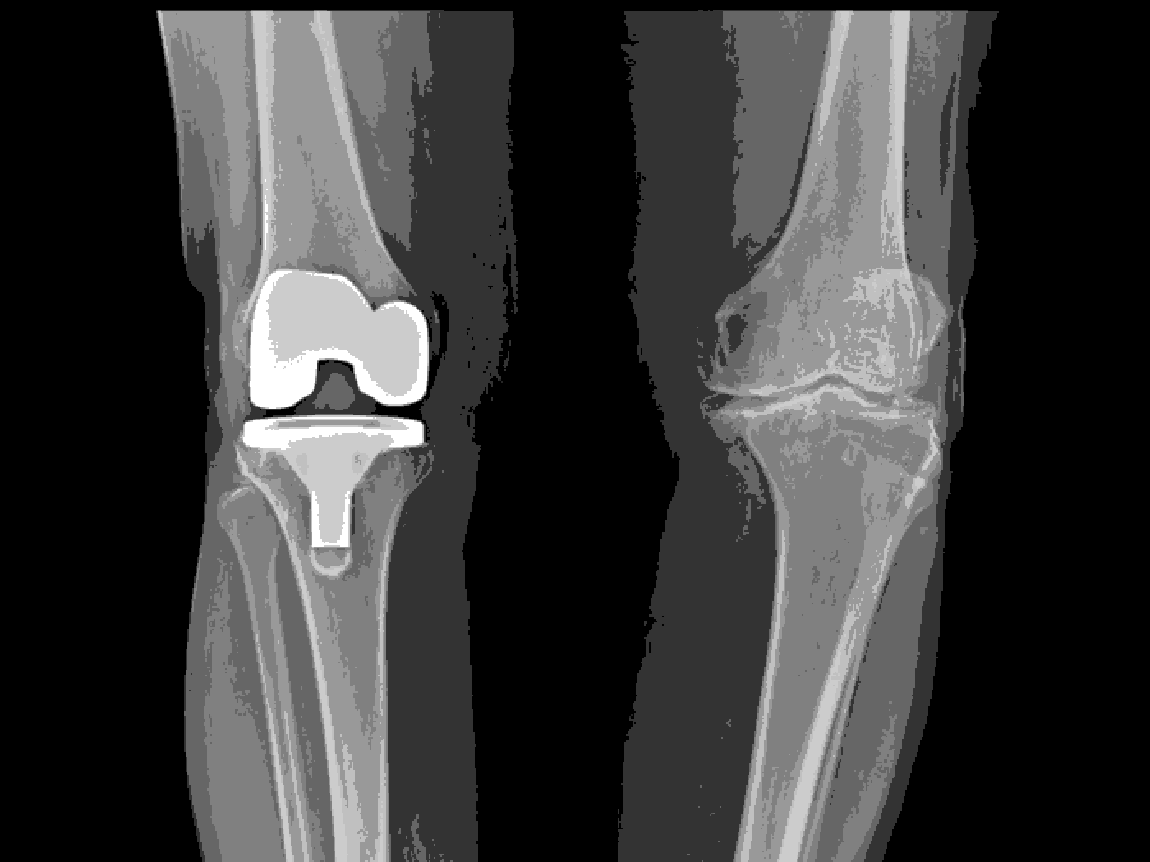

Options: Total or partial knee replacement. Arthroscopy (keyhole surgery) is not recommended for OA alone.